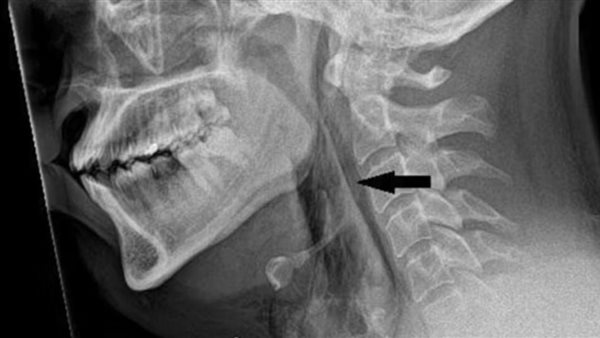

في الحالة الأخيرة، التي أبلغ عنها الأطباء في مستشفى ناينويلز باسكتلندا، زار المريض المستشفى وهو يشكو من آلام شديدة في الرقبة مرتبطة بالعطس، لكن لاحظ الأطباء صوت طقطقة خافت عندما تحسسوا رقبته، والتي لم يتمكن الرجل من تحريكها بشكل صحيح، وعلى إثر ذلك كشفت عمليات المسح عن تمزق صغير في القصبة الهوائية للرجل يبلغ عرضه حوالي حبة السمسم، وارتفع الضغط في الشعب الهوائية بما يصل إلى 20 مرة أعلى من المعتاد، وذلك بسبب تأثير حبس العطس.

اشتبه الأطباء في أن القصبة الهوائية مثقوبة بسبب التراكم السريع للضغط في القصبة الهوائية أثناء العطس مع أنف مقروص وفم مغلق، وفي تلك الحالة يفكر الأطباء الذين يعالجون تمزق القصبة الهوائية في إجراء عملية جراحية إذا كان المريض لا يستطيع التنفس من تلقاء نفسه أو إذا امتد التمزق إلى المساحة المحيطة بالرئتين، وهناك حاجة أيضًا إلى إجراء عملية جراحية إذا كان هناك تراكم مستمر للهواء تحت الجلد أو داخل الصدر.